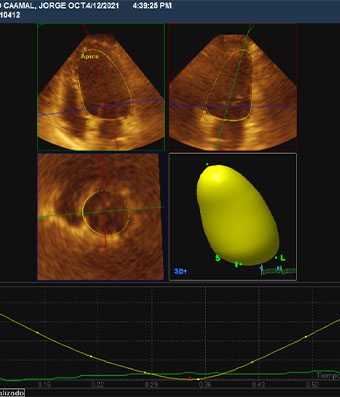

Ecocardiografía

El ecocardiograma o ecocardiografía utiliza ondas sonoras de alta frecuencia para obtener imágenes del corazón en vivo y que son proyectadas en una pantalla. Este auxiliar diagnóstico aporta información en 30 a 60 minutos de la forma, tamaño, función y movimiento del corazón así como de sus estructuras internas, como por ejemplo las válvulas cardiacas. Este estudio es seguro en pacientes adultos, en pacientes pediátricos (ecocardiograma pediátrico) o incluso en mujeres embazadas para estudiar el desarrollo del corazón del bebé en la cavidad uterina (ecocardiografía fetal).

Las imágenes ecocardiografías del corazón pueden ser obtenidas en diferentes modos (unidimensional, bidimensional o tridimensional, Doppler, Doppler color), utilizando una sonda externa (ecocardiograma transtorácico) o una sonda interna (ecocardiograma transesofágico) y puede ser adquirido en reposo, en estrés con esfuerzo físico o con el uso de medicamentos (estrés con dobutamina), dependiendo del diagnóstico y de la indicación de tú médico.